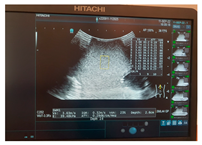

| Ultrasound | ![]() | ![]() | ![]() |